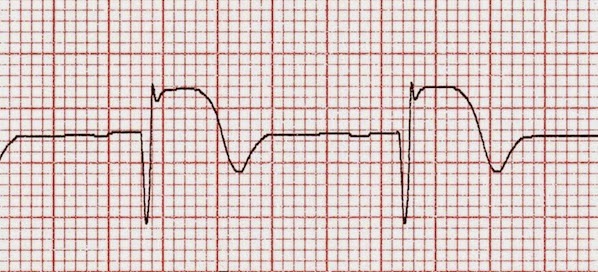

En infarto de miocardio con shock cardiogénico, el tratamiento percutáneo del vaso responsable solamente dio mejor resultado que la intervención inicial en múltiples vasos. New England Journal of Medicine, 21 de diciembre de 2017